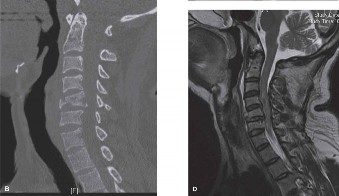

Screening for Noncontiguous Fractures

A frequently tested and clinically vital concept in spine trauma is the incidence of noncontiguous spinal fractures. When a patient presents with a primary spinal fracture, what is the rate of finding a second, separate fracture at a non-adjacent level? The literature reports this rate to be between 10% and 22%, with 15% being the most commonly cited average. This high incidence mandates that the entire neuroaxis—from the occiput to the sacrum—be imaged and scrutinized. In our patient, the whole-spine CT protocol ruled out any cervical or additional thoracic/lumbar fractures, but failing to screen the entire spine is a classic pitfall that leads to missed injuries and devastating outcomes.